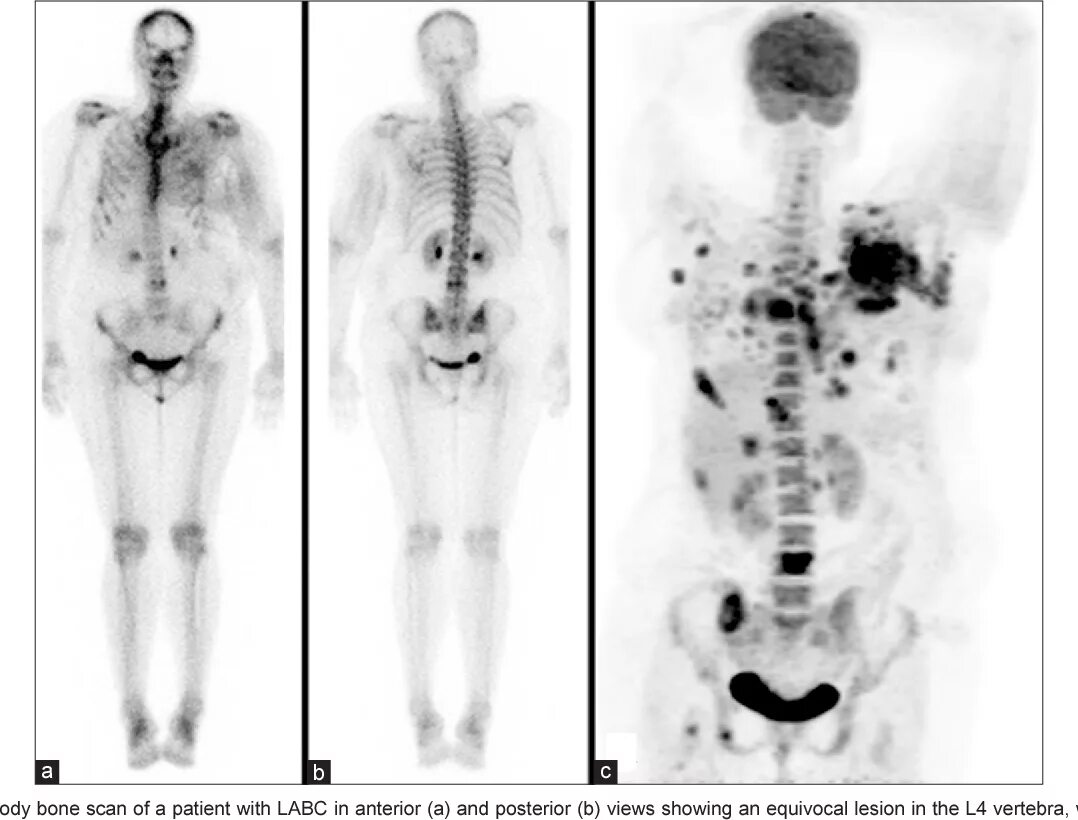

Метастазы в костях при раке предстательной железы